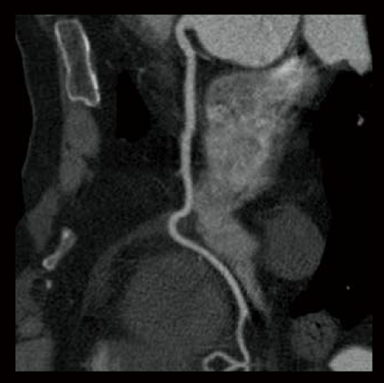

Dans les examens TDM cardiaques, les différents facteurs tels que la fréquence cardiaque et les mouvements du cœur affectent la qualité de l’image. Avec les méthodes conventionnelles de reconstruction d’image, des artères coronaires non focalisées et des artefacts causés par le mouvement peuvent apparaître, ce qui se traduit par des images ne répondant pas à la qualité attendue, ce qui peut affecter le diagnostic. Pour résoudre ces problèmes, Fujifilm a développé Cardio StillShot, qui calcule la direction et la quantité de mouvement du sujet en quatre dimensions à partir des données brutes collectées pendant les examens TDM cardiaques, et les corrige pendant la reconstruction de l’image pour obtenir une résolution temporelle effective de 28 msec.*1 La résolution temporelle effective contribue à améliorer la capacité de diagnostic en fournissant des images cliniques focalisées de haute définition avec moins d’artefacts de mouvement, même chez les patients ayant une fréquence cardiaque élevée.

Cardio StillShot : OFF

Cardio StillShot : ON